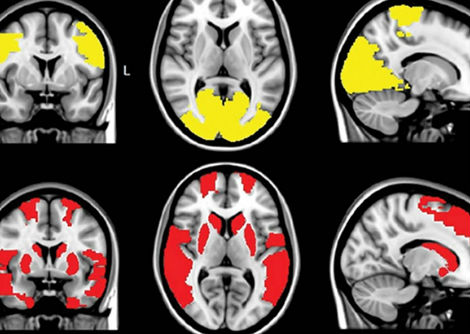

على الرغم من التقدم المحرز، لا تزال هناك عقبات كبيرة. فالحركة البراونية تُصعّب التحكم الدقيق، والعديد من روبوتات الحمض النووي الحالية لا تزال أنظمة ثابتة ومعزولة ذات وظائف محدودة. كما يفتقر هذا المجال إلى بنية تحتية داعمة قوية، بما في ذلك قواعد بيانات مفصلة للخصائص الميكانيكية للحمض النووي وأدوات محاكاة قادرة على التنبؤ بدقة بكيفية عمل هذه الآلات.